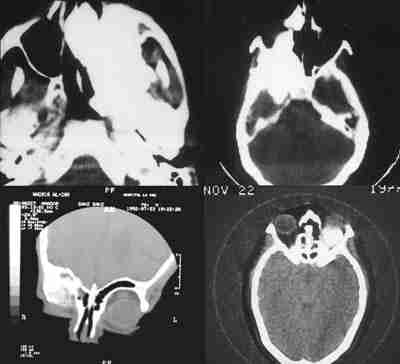

Figura 8. Las técnicas neurorradiológicas son fundamentales en la

cirugía de la órbita.